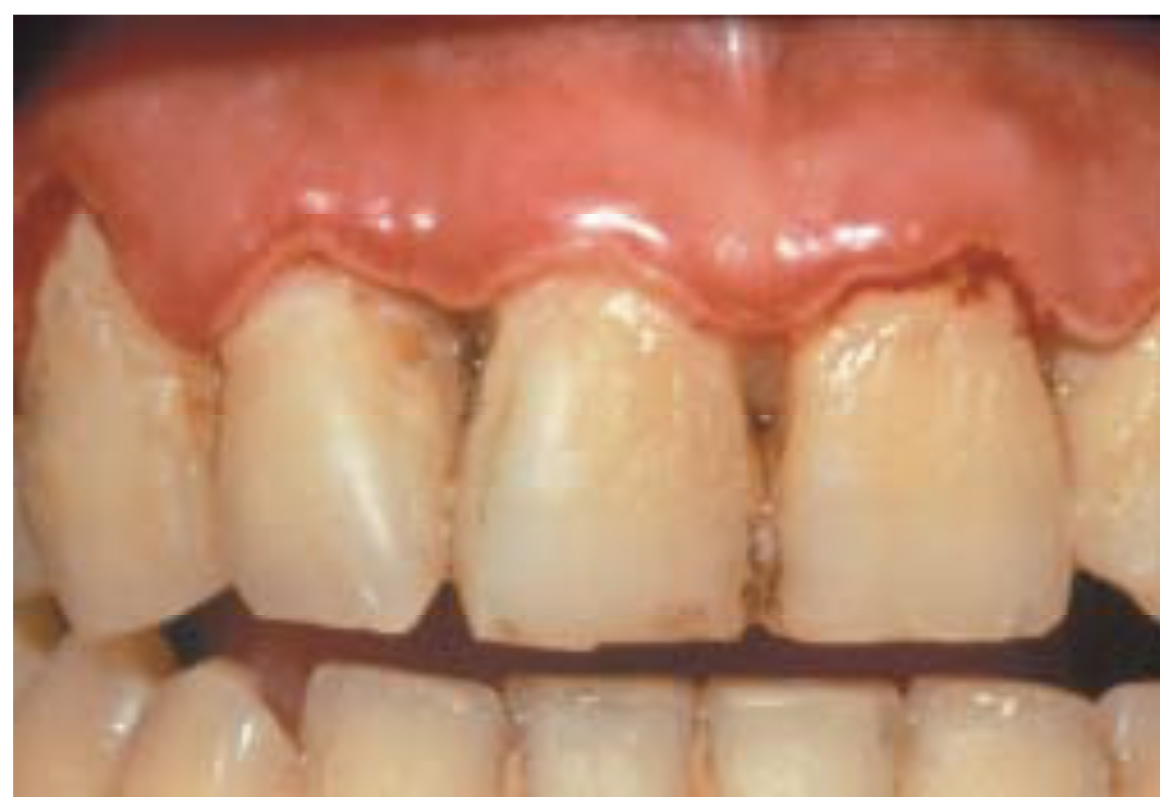

Gingivitis Necrotizante . Symptoms are acute pain, bleeding, and foul breath. Los síntomas son dolor agudo, sangrado y aliento de olor. Diagnosis is based on clinical findings. Treatment is gentle debridement, improved oral hygiene, mouth rinses, supportive care, and, if debridement must be delayed, antibiotics. La gingivitis ulcerativa necrosante aguda es una infección dolorosa de las encías. Acute necrotizing ulcerative gingivitis (anug) is a rare infectious disease of the gum tissue, affecting <1% of the population. Covers the management of acute necrotizing ulcerative gingivitis where the gums are acutely painful and swollen; The aim of this narrative literature review was to describe the available evidence on the diagnosis and treatment of ng, and present. Anug presents as an acute, painful, and destructive. They bleed easily and have. There are three major forms: It has an acute clinical presentation with the distinctive. Acute necrotizing ulcerative gingivitis is a painful infection of the gums. Necrotizing ulcerative gingivitis (nug) is a typical form of periodontal diseases.

Gingivitis Necrotizante La gingivitis ulcerativa necrosante aguda es una infección dolorosa de las encías. It has an acute clinical presentation with the distinctive. Diagnosis is based on clinical findings. They bleed easily and have. La gingivitis ulcerativa necrosante aguda es una infección dolorosa de las encías. Acute necrotizing ulcerative gingivitis is a painful infection of the gums. There are three major forms: The aim of this narrative literature review was to describe the available evidence on the diagnosis and treatment of ng, and present. Treatment is gentle debridement, improved oral hygiene, mouth rinses, supportive care, and, if debridement must be delayed, antibiotics. Anug presents as an acute, painful, and destructive. Symptoms are acute pain, bleeding, and foul breath. Covers the management of acute necrotizing ulcerative gingivitis where the gums are acutely painful and swollen; Los síntomas son dolor agudo, sangrado y aliento de olor. Necrotizing ulcerative gingivitis (nug) is a typical form of periodontal diseases. Acute necrotizing ulcerative gingivitis (anug) is a rare infectious disease of the gum tissue, affecting <1% of the population.